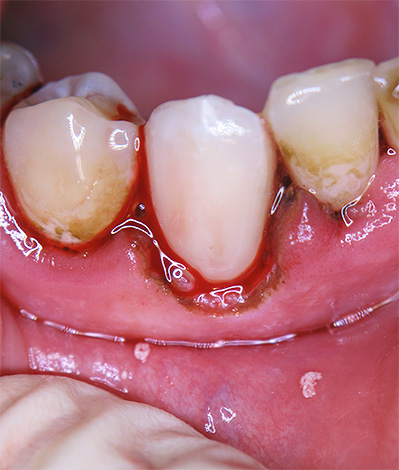

Na foto, você pode comparar o defeito em forma de cunha e a cárie cervical:

É importante distinguir entre um defeito em forma de cunha e cárie cervical: eles diferem em que o primeiro está na forma de uma cunha ou em forma de V. Com um defeito em forma de cunha, as paredes da cavidade são densas, lisas e brilhantes, o que não se pode dizer sobre a destruição cariosa do dente na região cervical.

Apesar de a localização dessas doenças ser a mesma, a aparência da cavidade sempre informa ao médico o diagnóstico correto. Além disso, as formas iniciais de cárie e um defeito em forma de cunha podem ser reconhecidas quando manchadas com indicadores especiais de cárie.